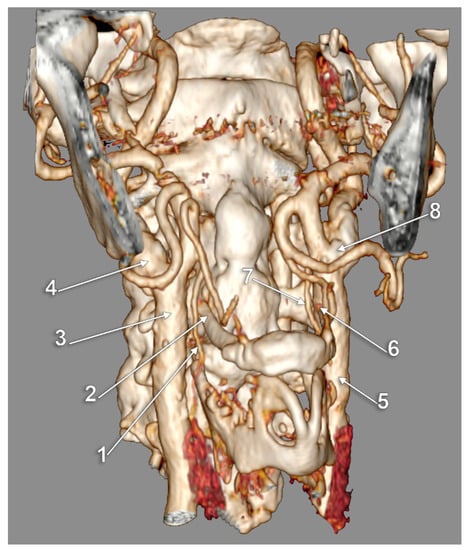

The Carotid–Hyoid Topography Is Variable

Manta, M.D.; Rusu, M.C.; Hostiuc, S.; Vrapciu, A.D.; Manta, B.A.; Jianu, A.M. The Carotid–Hyoid Topography Is Variable. Medicina 2023, 59, 1494. https://doi.org/10.3390/medicina59081494